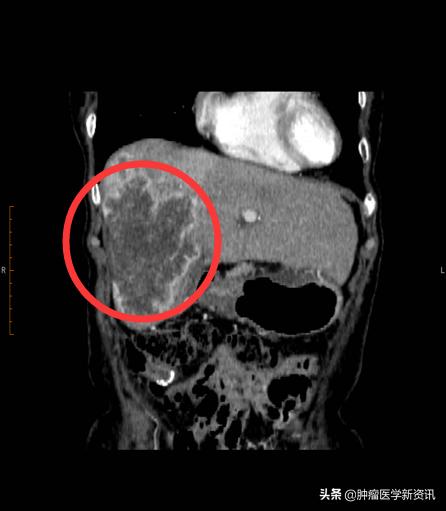

原本以为母亲的病情稳定了,不料,打击接踵而来。2019年9月,复查结果显示肝右叶占位,发生肝转移,双肾多发小那囊肿同前,肿瘤标志物CEA>500,CYFRA21-1上升到了15.27,CA19-9>800,CA242>500,CA72-4>250,NSE为40.31,病情发生恶化。一向坚强的王女士母亲,开始变得疑虑焦躁。11月,主治医生建议使用贝伐单抗+奥沙利铂化疗,病灶缩小后进行手术。这意味着,王女士的母亲需要继续新一轮的化疗和手术,继续承受治疗带来的身心痛苦。这一次,王女士拒绝了,她说我真的不忍心看母亲再受折磨了。

治疗前

2020年3月,王女士母亲在持续进行2次iNKT癌症免疫治疗+肝部介入后,2个月的时间,王女士的母亲肝部10cm肿瘤缩小了1/3,肿瘤标志物下降接近一半,精神也越来越好,就连吃饭都比之前好多了,可以如正常人般生活了。